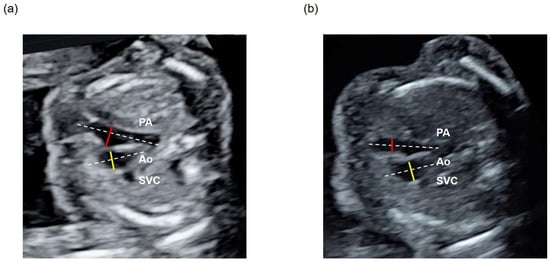

3.2. Calculation and Assessment of the PA/Ao Ratio